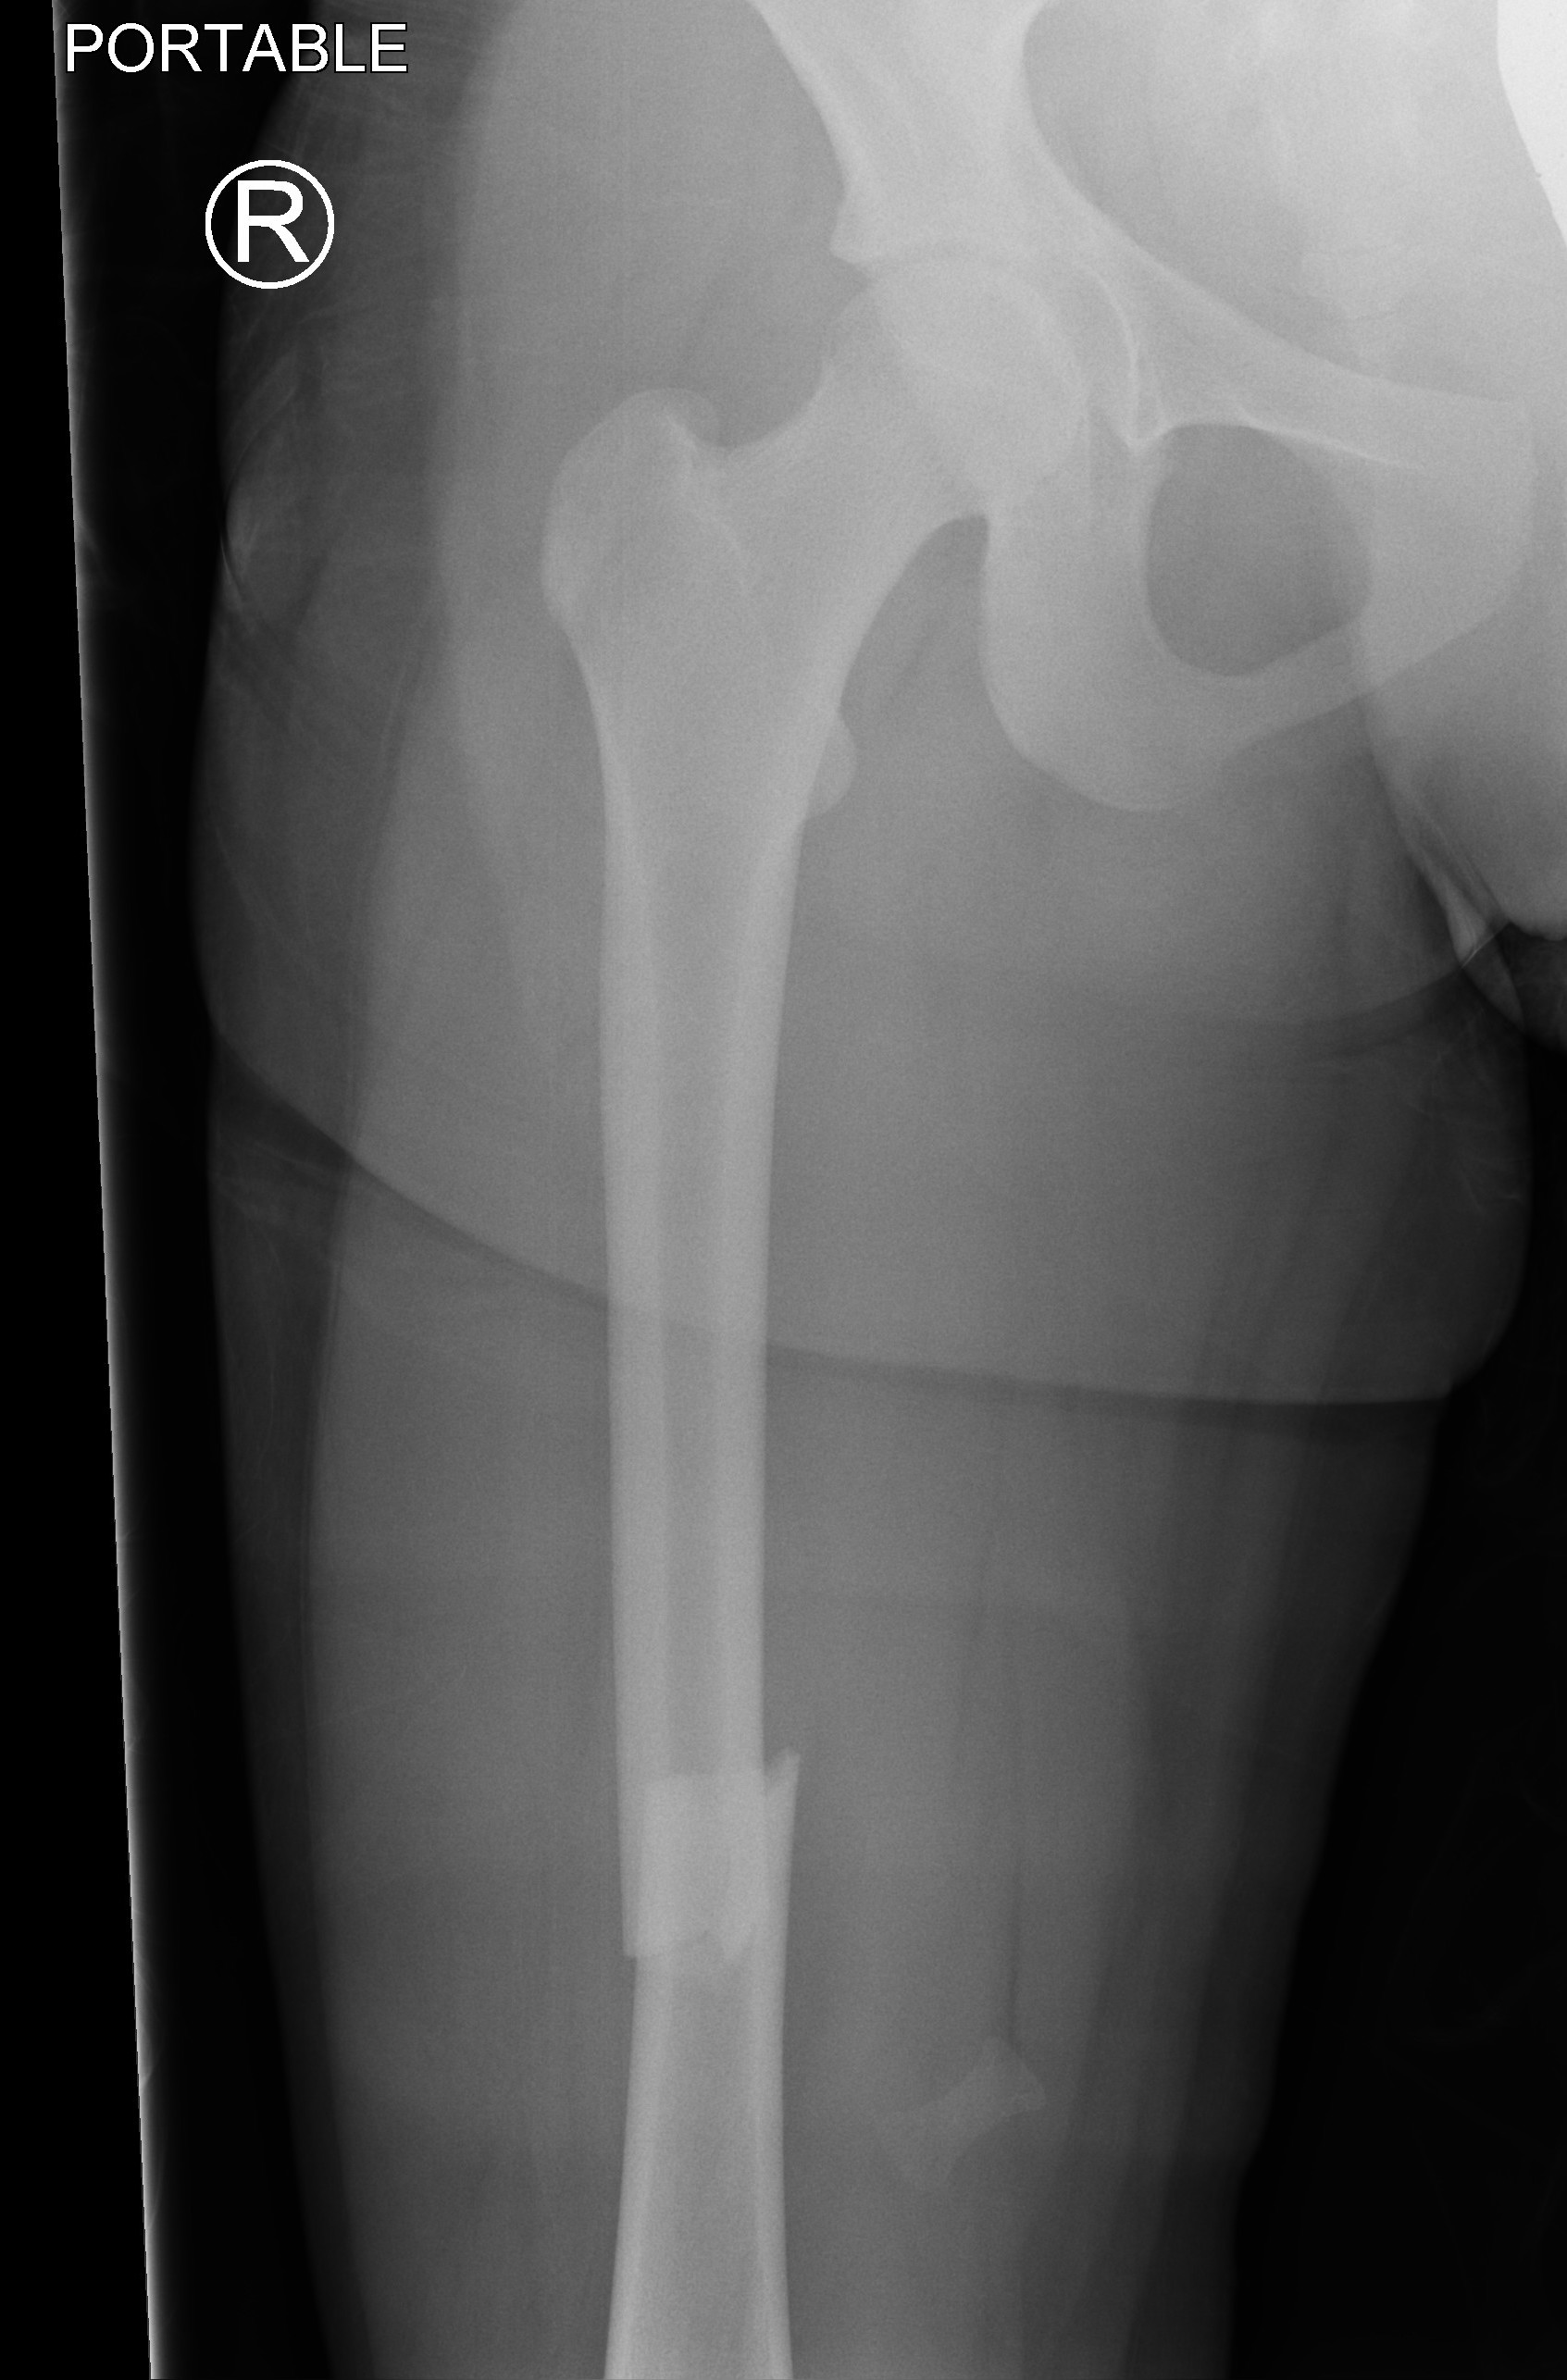

Subtrochanteric fractures

Issues

Non operative treatment rarely indicated in older children as acceptable alignment hard to maintain

Options

Plate v TENS

- no difference in outcome between plate and TENS

- plate patients tended to be older and heavier

Li et al J Pediatr Orthop B 2013

- 54 children aged 5 - 12 with subtrochanteric fractures

- better outcomes and lower complication rate with plate compared to TENS